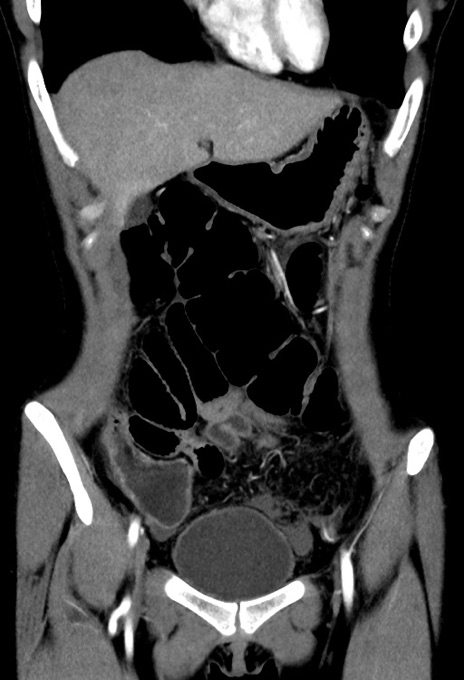

症例17(冠状断像)

【症例】20歳代女性

【主訴】嘔吐、下腹部痛

【現病歴】昨日夕食後に嘔吐し下腹部痛が出現。本日になっても嘔吐持続し改善しないため来院。

【身体所見】意識清明、BT 37.2℃、BP 108/67mmHg、腹部:平坦、やや硬、下腹部正中から右にかけて圧痛あり、反跳痛軽度あり、tapping pain(+)。

【データ】WBC 13600、CRP 14.94